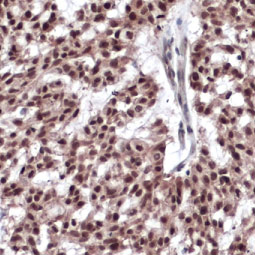

Vimentin antibody [GT812]